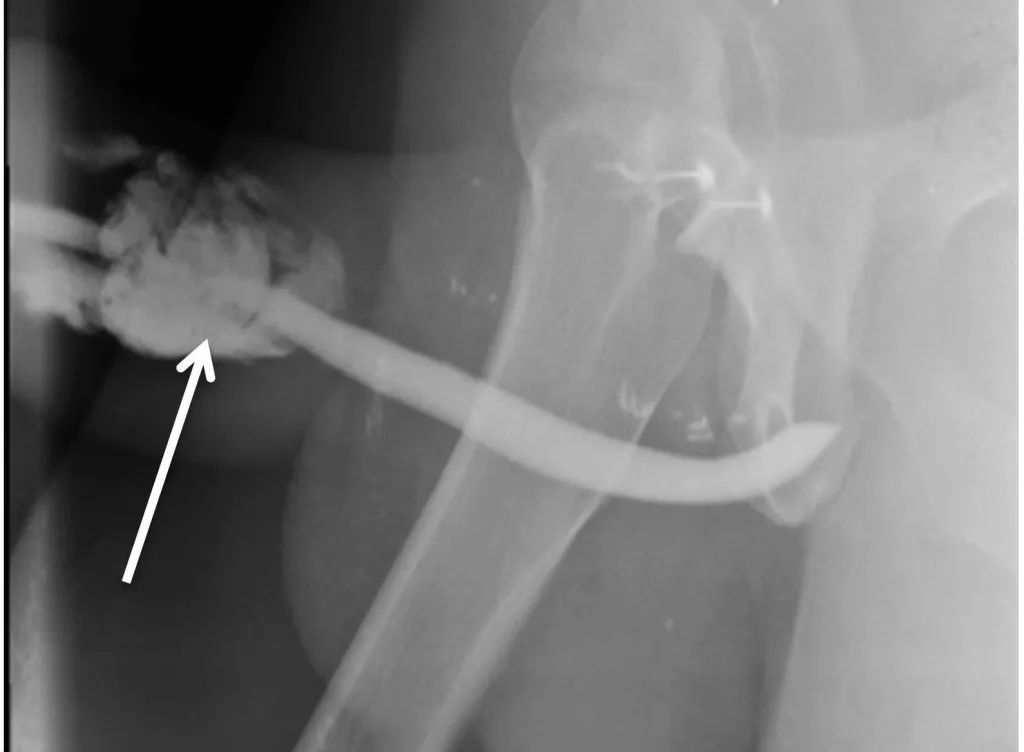

A fratura do pênis é uma emergência urológica incomum, definida como ruptura da cartilagem peniana devido a trauma contuso no órgão ereto.

A cartilagem peniana, também chamada de túnica albugínea, uma estrutura resistente, formada por duas lâminas, que recobre os dois corpos cavernosos e o corpo esponjoso.